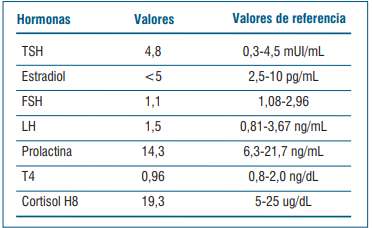

Se realiza dosificación de hormonas evidenciando una respuesta insuficiente de la GH al ejercicio y gonadotrofinas en valores prepuberales (tabla 1). El cortisol basal está en zona gris (entre 3-15 mcg/dl). Se solicitó test de estímulo con hormona adrenocorticotrópica (ACTH) para valorar insuficiencia suprarrenal (cortisol posestímulo de ACTH <18 mcg/dl), que no se realizó. En la evolución se revaloró cortisol y fue suficiente (≥15 mcg/dl).

No presenta clínica de déficit de hormona antidiurética, presenta ionograma y densidad urinaria sin alteraciones. No alteración de otros ejes hipofisarios (tabla 2).